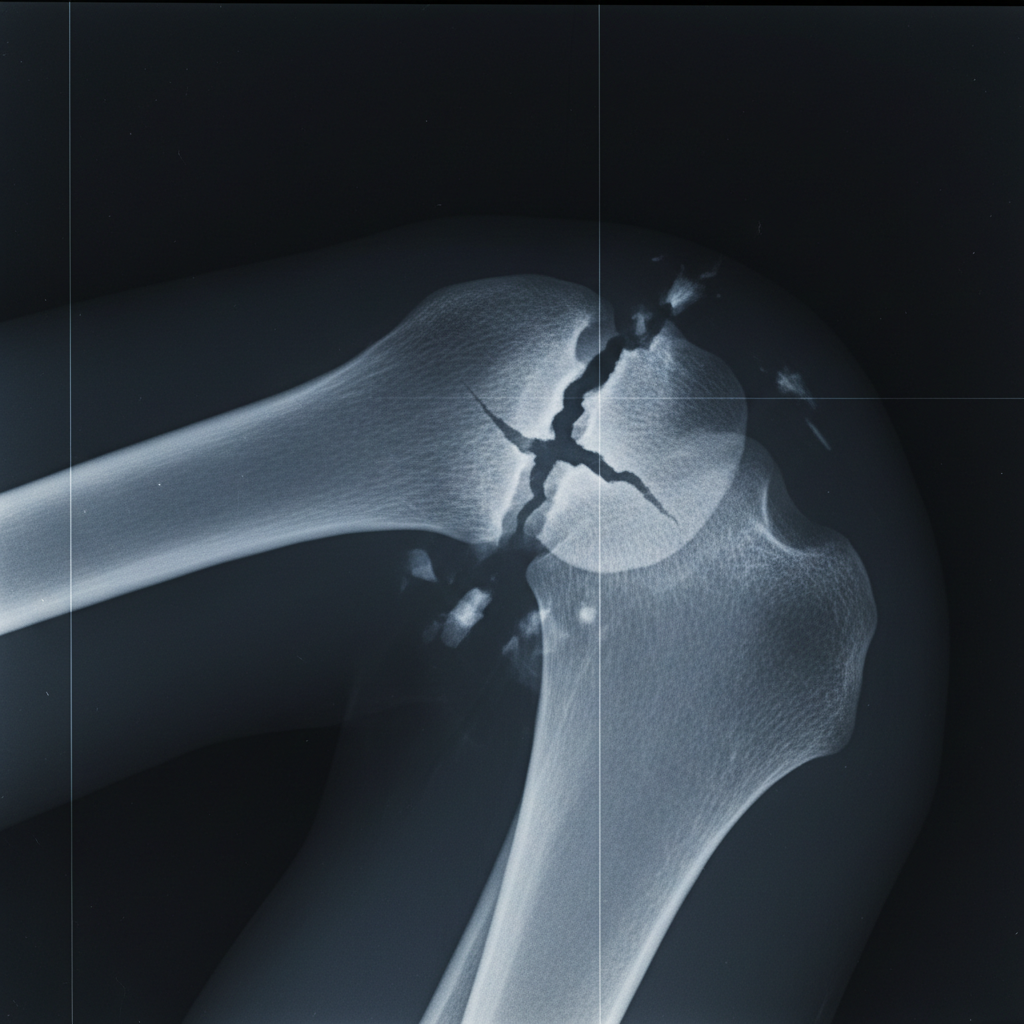

Podstawowy błąd, który popełnia większość osób? Utożsamianie pęknięcia kości ze złamaniem i odwrotnie. Choć oba te urazy oznaczają przerwanie integralności tkanki kostnej, różnica leży w stopniu i charakterze uszkodzenia. Pęknięcie kości to niecałkowite przerwanie jej ciągłości – często przybiera formę rysy lub szczeliny, która nie rozdziela całej kości na dwie części. Złamanie natomiast to całkowite oddzielenie fragmentów kości, często z przemieszczeniem i większym krwawieniem. Według praktyków ortopedii, każde przerwanie ciągłości kości – także pęknięcie – traktowane jest jednak jako forma złamania, choć z inną ścieżką leczenia i powikłań.

| Diagnoza | Często problematyczna, subtelne zmiany | Zazwyczaj oczywista w RTG |

Warto pamiętać, że pęknięcie może być trudne do wykrycia bez profesjonalnej diagnostyki. Objawy są często niespecyficzne: lekki obrzęk, umiarkowany ból, uczucie niestabilności. Według Medme, pęknięcie kości promieniowej zdarza się wyjątkowo często podczas banalnych upadków, szczególnie u kobiet po 50. roku życia.

Pęknięcie kości to mistrz kamuflażu. Kluczowe symptomy bywają mylące, zwłaszcza kiedy uraz dotyczy drobnych kości stopy, nadgarstka czy palców. Według drjerzakowski.pl, najczęstsze objawy to:

- Uporczywy, narastający ból nasilający się przy obciążeniu

- Niewielki, ale utrzymujący się obrzęk

- Trudność w wykonywaniu pełnego zakresu ruchów

- Często brak widocznej deformacji lub krwiaka

- Uczucie „przeskakiwania” lub niestabilności w stawie

Z tych powodów, nawet doświadczeni sportowcy potrafią przez kilka dni ignorować uraz, tłumacząc go zmęczeniem czy przeciążeniem.